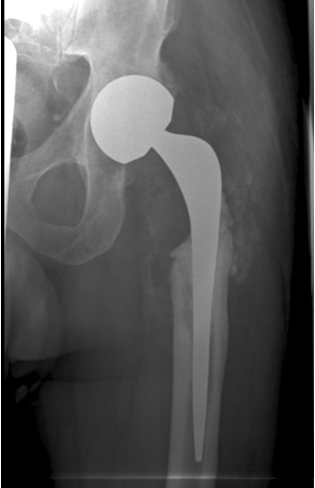

- 6/2010: Cementless revision THR (Acetabular component: Metallsockel 2000, Orthodynamics, Luebeck, Germany; Femoral component: Restoration Modular Stryker, Mahwah, NJ, USA). Microbiology: Five tissue samples and PCR/culture of the spacer sonication fluid without detection of microorganisms

- 7/2011: Clinical and radiological follow-up one year after reimplantation: no clinical or laboratory signs of a relapse of the periprosthetic infection. The X-rays (Figure 4 [Fig. 4]) show moderate ossifications of the soft tissue around the femoral diaphysis without clinical relevance. No signs of implant-loosening or migration.

Figure 4: Cementless total hip revision implant: radiological follow-up 1 year after implantation